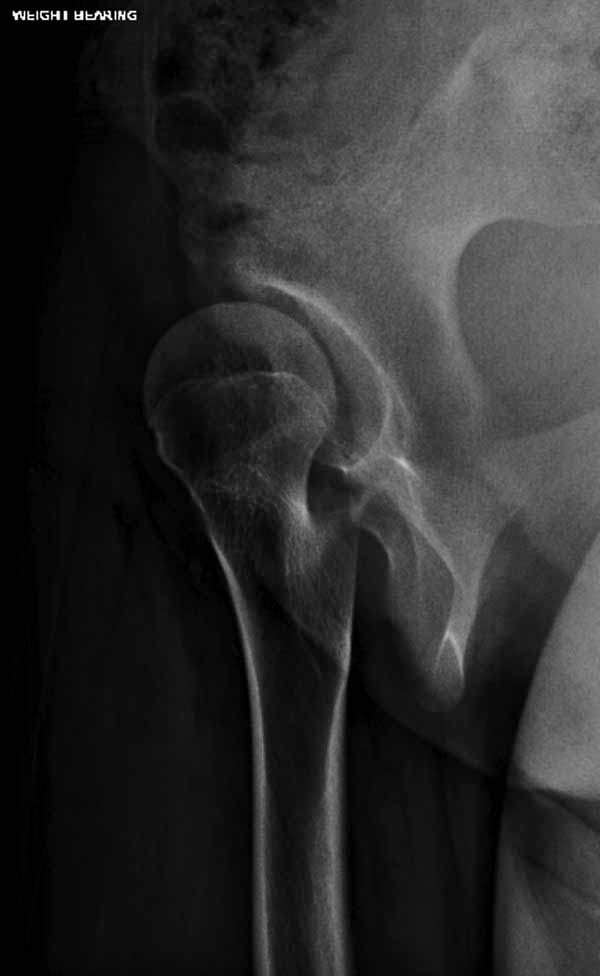

Жалобы на двухсторонние постоянные боли при нагрузке и неустойчивость. Внутренная ротация конечности в суставе более 40 градусов и на рентгенограмме двухсторонний подвывих головки с нарушением линии Шентона, а на боковом снимке с минусовым покрытием головки. МРТ - удлиненная связка и импинджмент (бугор) в шейке.